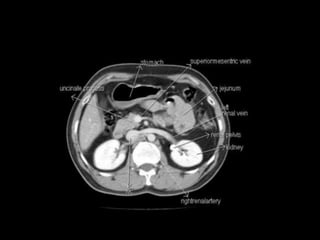

Cross section anatomy of abdominal ct scan

Cross section anatomyof abdominal ct scan